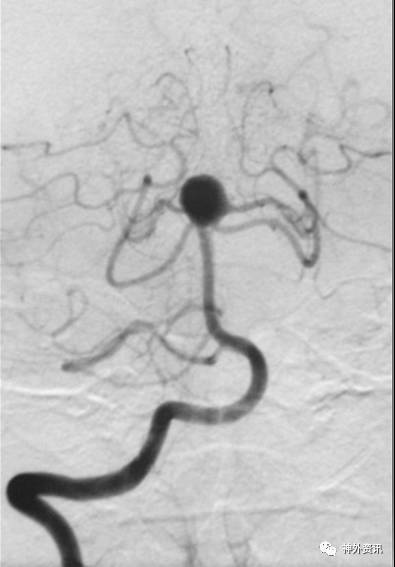

猪尾塑形

猪尾左行和右行

微导管尾端向下直立,头端向前弯曲时,头端相对左偏为左行,右偏为右行。

指向下方的颈内动脉眼段或床突段动脉瘤(颈动脉窝动脉瘤)

指向下方的颈内动脉后交通段或脉络膜段动脉瘤

(1)左侧颈内动脉-猪尾左行

(2)右侧颈内动脉-猪尾右行

病例一